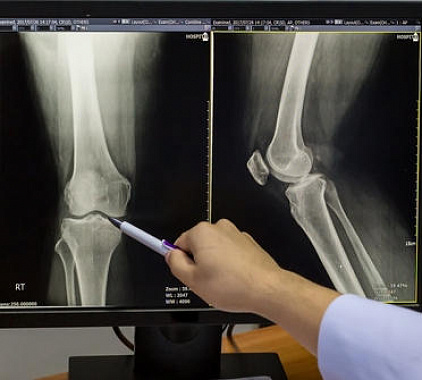

Фотогалерея

Врач размещается в рядом находящейся комнате. При необходимости. он просит больного задержать дыхание и делает снимки. В большинстве случаев сразу получают рентгенограммы в боковой и прямой проекции. При необходимости проводят сканирование в других позициях. Совершают прицельный снимок. Выполняют рентген с нагрузкой.

Результатом диагностики является подробный протокол. Врач описывает состояние костей, их контуры, отражает ширину суставной щели, рядом находящиеся элементы. Также врач указывает точные характеристики выявленных нарушений. Пишет свои выводы и рекомендации.